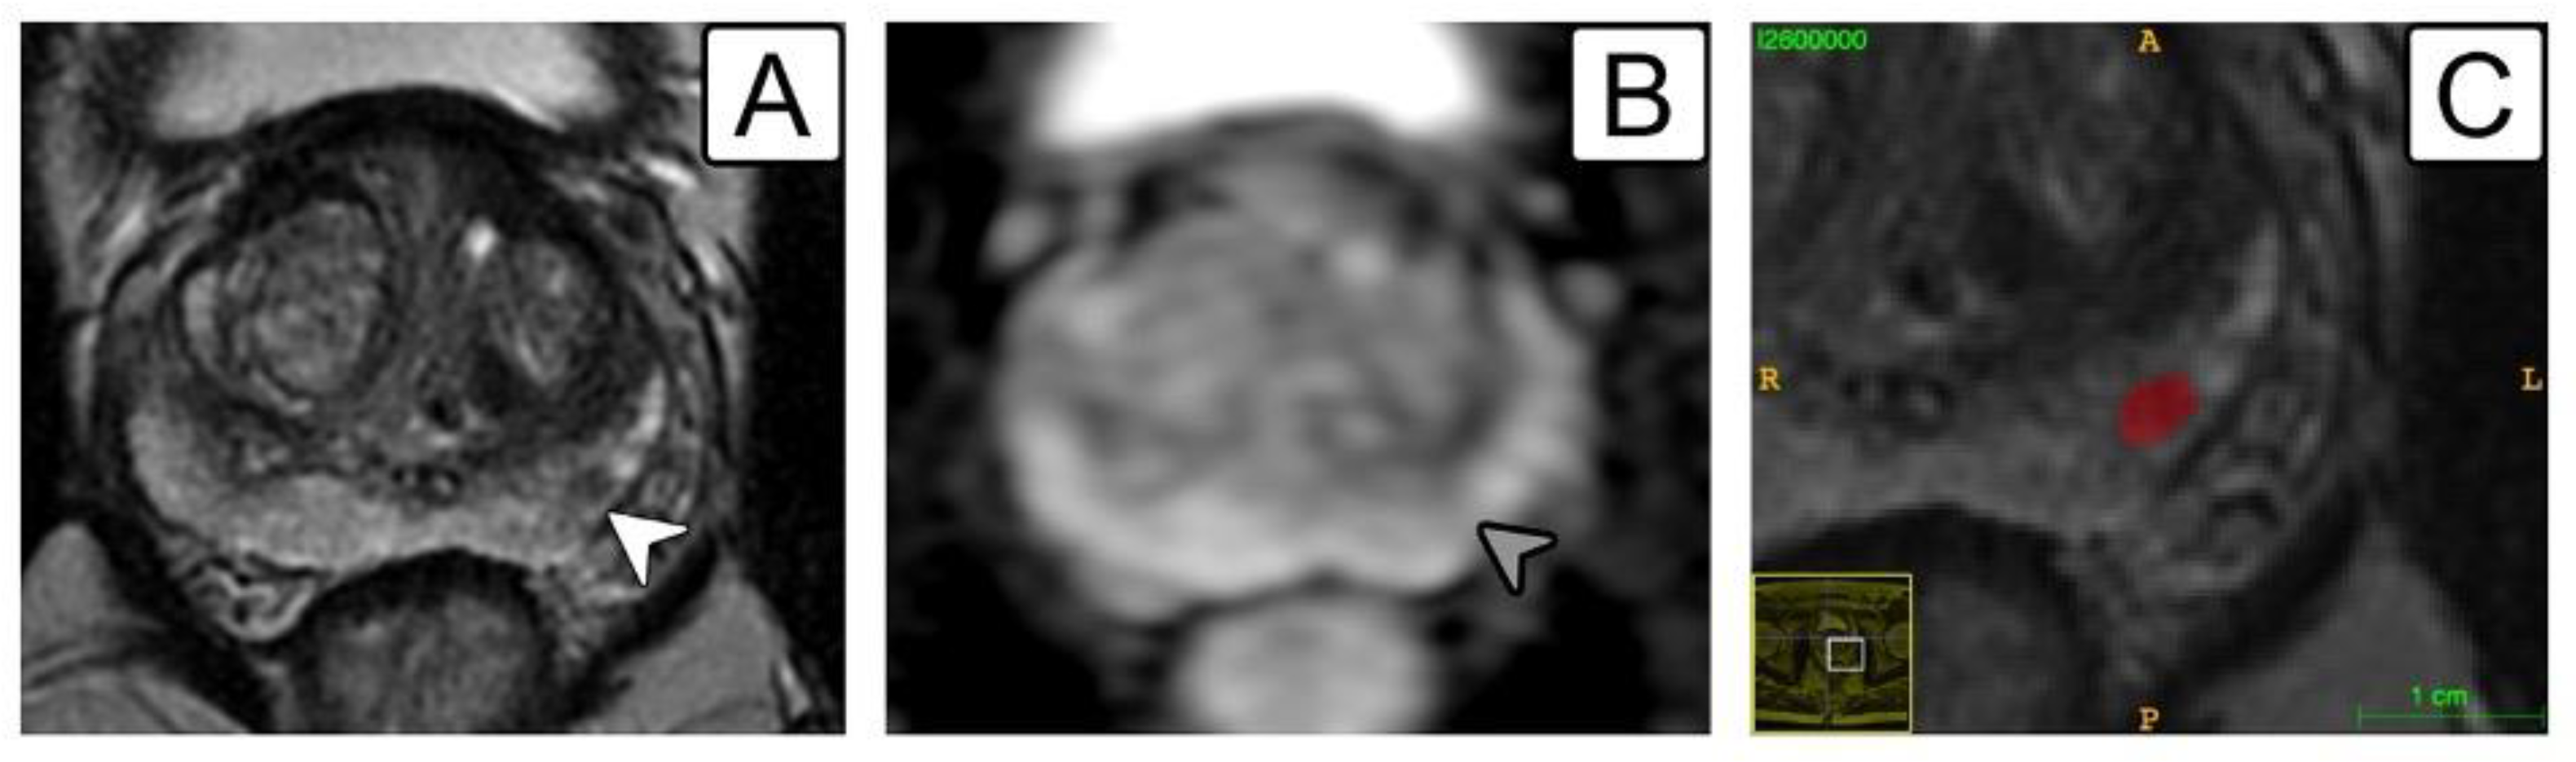

2.4. Lesion Segmentation